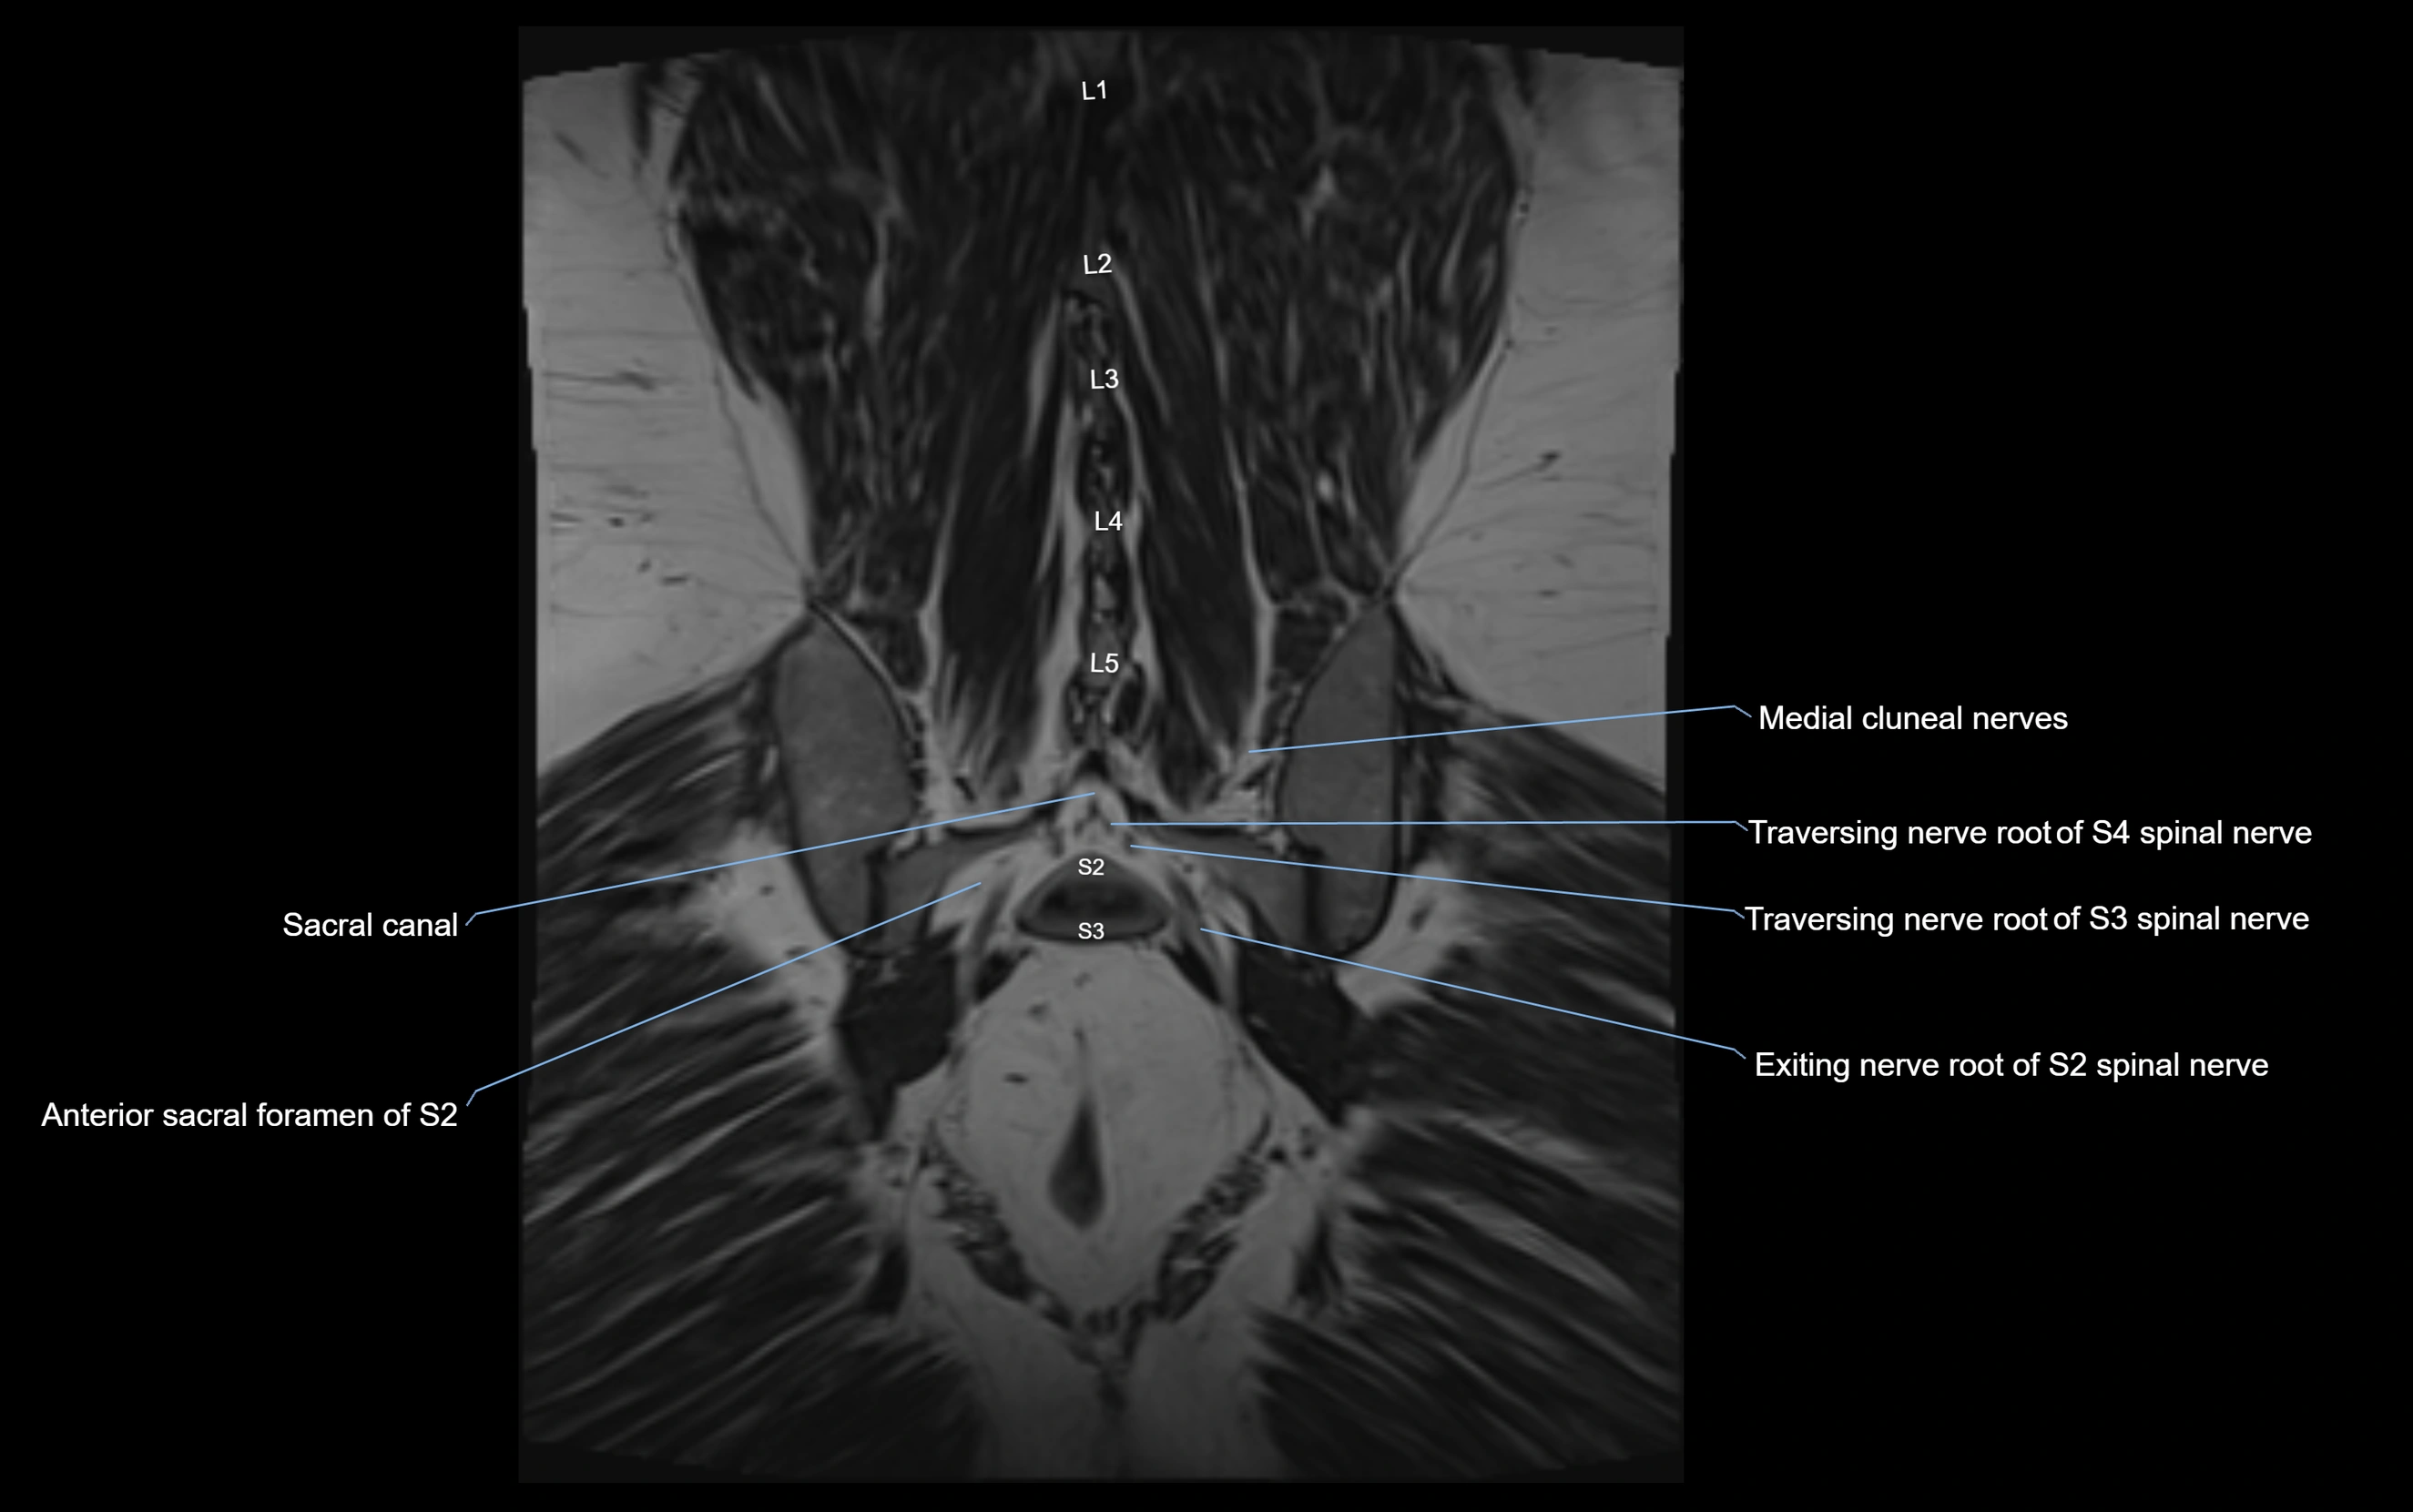

MRI Appearance

T1-weighted images:

• Nerve appears as a very thin low-to-intermediate signal intensity structure

• Surrounded by bright fat, aiding visualization

T2-weighted images:

• Nerve shows intermediate to mildly hyperintense signal compared to muscle

• Pathological involvement appears brighter

STIR (Short Tau Inversion Recovery):

• Normal nerve appears dark

• Inflamed or entrapped nerve appears bright hyperintense

T1 Fat-Sat Post-Contrast:

• Normal nerve enhances minimally

• Pathologic nerve (neuritis, entrapment, tumor infiltration) shows focal or diffuse enhancement

3D T2 SPACE / CISS:

• Nerve appears intermediate to mildly hyperintense compared to muscle

• Surrounded by bright fat or CSF, improving visualization

• Best sequence for mapping small pelvic nerves such as the anococcygeal